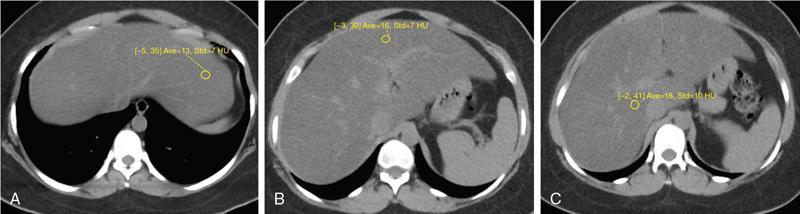

Excessive triglyceride accumulation within hepatocytes is defined as hepatic steatosis. Major conditions associated with hepatic steatosis include alcoholic fatty liver disease (AFLD) and nonalcoholic fatty liver disease (NAFLD). Causes of hepatic steatosis are discussed in Table 9.10.3. NAFLD is the most common form of hepatic steatosis and discussed in detail below. Up to 90% of patients with chronic alcoholic intake have fatty liver. Those with pure AFLD have a 10% risk of progressing to cirrhosis. Consumption of 30 g ethanol/day shows increased risk of chronic liver disease and cirrhosis. Other risk factors include female sex, obesity, cigarette smoking, obesity and associated risk factors. These factors are divided into 2 main categories which can cause fatty liver: inborn errors of metabolism and acquired metabolic disorders. Inborn errors of metabolism include abetalipoproteinemia, galactosemia, glycogen storage disease, hereditary fructose intolerance, homocystinuria and Wilson disease. Inflammatory bowel disease, jejunoileal bypass, malnutrition, starvation and total parenteral nutrition are acquired metabolic factors associated with increased risk. Chronic HCV infection, is associated with hepatic steatosis, with prevalence of 40%–80%. Hepatic steatosis can be seen as an adverse reaction to some medications such as tetracycline, valproic acid, some of chemotherapeutic agents, dexamethasone, amiodarone, methotrexate, tamoxifen and acetylsalicylic acid. Either microvesicular or macrovesicular steatosis can be observed in drug-induced hepatic steatosis. It generally occurs with therapy lasting several weeks or months and is reversible after discontinuation. The leading cause of hepatic steatosis in paediatric population is NAFLD. Six per cent of these patients develop cirrhosis and end-stage disease. Other less common causes include starvation and malnutrition, drugs (glucocorticoids, oestrogens, tetracyclines, and methotrexate), intoxications (carbon tetrachloride, organic phosphates, organic solvents, and alcohol), metabolic disorders, hepatitis C infection, and total parenteral nutrition. NAFLD is defined as steatosis affecting >5% of hepatocytes in the absence of a secondary cause. NAFLD represents a spectrum of disease, ranging from simple steatosis to steatohepatitis through to fibrosis and cirrhosis and in some cases hepatocellular carcinoma. NAFLD is a growing epidemic worldwide in part due to obesity and insulin resistance leading to liver accumulation of triglycerides and free fatty acids. Nonalcoholic steatohepatitis (NASH) is defined by histologic terms as a necroinflammatory process whereby the liver cells become injured in a background of steatosis. 20% of patients with NAFL progress to NASH, which progresses to fibrosis and cirrhosis over a 15-year time period (Fig. 9.10.3). The definition of NAFLD requires imaging or histology evidence of steatosis and no causes for secondary hepatic fat accumulation like significant alcohol intake, drugs or hereditary disorders (Table 9.10.4). The incidence of NAFLD ranges from 20% to 30% in Western countries and 5%–18% in Asia. As it currently stands, NAFLD represents the second most common reason to be listed for a liver transplant. The prevalence of NAFLD is higher in patients with obesity, diabetes, and patients with hyperlipidaemia. Prevalence increase with age from less than 20% at age 20 to more than 40% over 60 years of age. Males show a higher risk for progression to NASH and fibrosis (Table 9.10.5). Up to 90% of patients with NAFLD have simple steatosis, and about 30% of patients with NAFL develop NASH, and in again about 30%–40% of NASH patients the disease progresses to manifest fibrosis and cirrhosis NAFLD related cirrhosis has a 10-year mortality of 25% and a 5% chance of developing end-stage liver disease and HCC. The theory implicated in the pathogenesis of NAFLD is the two-hit theory. Insulin resistance, enhanced dietary influx and increased hepatic lipogenesis leading to accumulation of triglycerides (TG) and FFA in the hepatocytes is the first hit. The lipid peroxidation, mitochondrial dysfunction and inflammation resulting in hepatocyte damage and development of liver fibrosis is the second hit. The stages of NAFLD on histology range from steatosis initially to hepatic fibrosis in late stages. In the steatotic stage large (macro-) and small (micro-) vesicles of fat, predominately triglycerides, accumulate within hepatocytes. The affected parenchyma is divided into thirds: 5%–33%, 34%–66% and >66% and graded as mild, moderate and respectively. Ballooned hepatocytes with accompanied steatosis and inflammation are characteristic of the steatohepatitis stage. Fibrosis has a characteristic appearance with early lesions showing a perisinusoidal deposition followed by periportal fibrosis which progresses to bridging. Raised GGT is the most common liver enzyme elevated in NAFLD. Transaminases are within normal range in 80% patients. No specific blood tests can diagnose NAFLD. Liver biopsy has remained the gold standard for diagnosis and quantification of liver fat. Drawbacks, however, include invasive nature, sampling error and procedure related complications like bleeding. Various imaging techniques are currently available in diagnosing and quantifying liver fat. MRI in particular proton density imaging and MR Spectroscopy have revolutionized imaging of fatty liver. Normal liver parenchyma is the same as or slightly more echogenic than the adjacent kidney and spleen. Fat deposition leads to increased echogenicity of liver. Decreased beam attenuation in patients with fatty change leads to poor visualization of structures such as intrahepatic vessels, bile ducts and liver lesions and in severe cases diaphragm (Table 9.10.6). Fatty liver can be graded on USG as: US has a fair accuracy of detecting the moderate to severe hepatic steatosis with sensitivity of about 90% and specificity of about 95% for patients without concomitant chronic liver disease. Ultrasound is observer and equipment dependent. Confounding factors such as large body hiatus may lead to overestimation of hepatic steatosis due to beam attenuation by overlying fat. Conditions like fibrosis, inflammation can affect interpretation. The ratio between the mean brightness level of liver and right kidney is called the Hepatorenal sonographic index. A cut off of 1.49 has a high sensitivity and specificity for diagnosis of steatosis >5%. The main advantages of CT for assessing steatosis are relatively fast acquisition, ease of performance, and quantitative results. Estimation of fatty liver is done on non-contrast enhanced images. The normal liver density is around 60 HU, which is approximately 10 HU higher than normal spleen. Fat accumulation in the liver manifests as proportionate decrease in density. Both the absolute and relative (to the spleen) values are used to characterize steatosis; a cut-off value of 40 HU has been suggested to predict fat content greater than 30% (Figs. 9.10.6 and 9.10.7) Attenuation difference between liver and spleen on unenhanced CT scan is a commonly used quantitative parameter to evaluate hepatic steatosis. This avoids errors in attenuation value measurement from different CT scanners and different reconstruction algorithms. Normal liver parenchymal attenuation on nonenhanced CT is slightly higher than the spleen. Liver attenuation progressively decreases as percentage steatosis increases (Table 9.10.7) (Fig. 9.10.8) Methods of liver fat quantification on CT have been discussed in details in chapter on liver transplant. Limited diagnostic accuracy for detecting mild degree hepatic steatosis is one of major drawback of CT. Disorders causing hyperdensity of liver such as iron, glycogen deposition can lead to errors in interpretation. The concomitant presence of iron and fat may not be accurately diagnosed on CT. Low CT density values may also be caused by oedema and inflammation. Likewise, the spleen is an imperfect reference standard as it can be affected by haemosiderosis and haemochromatosis in a small minority of patients. Dual-energy CT with its ability to perform material decomposition is more accurate in quantifying hepatic steatosis and allows staging of fibrosis. Imaging is done with two different energies (typically 80 kVp and 140 kVp). DECT has the potential to quantitate liver fat content independent of ROI (region of interest) placement. Magnetic resonance imaging (MRI) is presently the most accurate imaging modality for the evaluation of hepatic steatosis. Several different methods have been developed and introduced in MRI for the evaluation of hepatic steatosis. In this technique typically, two gradient echoes are acquired, one employing a TE in which the water peak (4.7 ppm) and the dominant fat peak (1.3 ppm) are ‘out of phase’ and hence subtractive (SOP), and the other using a TE in which the two peaks are ‘in phase’ and therefore additive (SIP). Because two echoes are acquired, this is often called ‘dual-phase’ or ‘dual echo’ imaging. Fat Signal Percentage is calculated as [SIP – SOP]/[2 × SIP] ×100. The dynamic range of magnitude based chemical shift techniques has typically a 0%–50% signal fat-fraction (Fig. 9.10.9) This technique uses both magnitude and phase information from three or more images acquired at different echo times appropriate for more accurate separation of water and fat signals as against only magnitude information in dual-echo. These methods provide estimates of fat fraction with a dynamic range of 0%–100%. Proton density Fat fraction (PDFF) is calculated as Sf/(Sw + Sf) where Sw = SI of the water component, Sf = SI of the fat component. PDFF specifically reflects the concentration of triglycerides in the hepatocytes as lipids within the other structures such as cell membranes and organelles are occult. Sensitivity up to 96% and specificity up to 100% for detecting any degree of steatosis have been reported. A fat-fraction threshold of 5.56% is commonly used to define steatosis; however, the optimal cut-off value still needs to be defined (Figs. 9.10.10 and 9.10.11). MRS can directly measure the chemical composition within tissue based on the frequency composition of the signal originated from the voxel of interest. Water proton peak appears as a single peak at 4.7 ppm, whereas fat peaks appear as multiple peaks around 1.3 ppm. PDFF can be calculated as the ratio of the sum of the signal intensities derived from the protons in fat divided by the sum of the signal intensities originated from the protons in both fat and water (Fig. 9.10.12). TABLE 9.10.8 MRS data are usually obtained from a single voxel manually placed in the liver parenchyma usually right posterior segment of the liver. Reported MRS sensitivities and specificities for detection of mild hepatic steatosis are 80.0%–91.0% and 80.2%–87.0%, respectively, outperforming CT and US. MRS can also provide excellent reproducibility of measurement. It is also unaffected by confounding factors like fibrosis, iron overload and glycogen. Small sample volume usually less than 3 × 3 × 3 cm3 is a major limitation of MRS, particularly in patients with uneven fatty change. Despite these practical limitations, MRS is considered to be the gold standard MR method for hepatic fat quantification. This is the most frequently encountered pattern and considering the homogenous involvement poses no diagnostic dilemma. Focal fat deposition and focal sparing in diffuse fatty liver are less common. These usually occur in specific locations like adjacent to falciform ligament or ligamentum venosum, in portal hepatis or gallbladder fossa. Imaging findings are suggestive of fatty pseudolesions rather than true masses. Occurrence in characteristic locations, absence of mass effect on vessels and structures, geographic configuration and contrast enhancement similar to or less than adjacent liver (Fig. 9.10.13). Fat deposition around insulinoma metastasis can occur as a local effect of insulin on the liver parenchyma. On ultrasound, it appears as an echogenic rim shows signal drop on out of phase images. Eisenberg has reported perilesional steatosis around focal nodular hyperplasia. Sometimes multiple small foci and seen scattered throughout the liver. These may appear as small round nodules (Fig. 9.10.14). Opposed phased imaging is more useful than CT or US to establish diagnosis. These may, however, pose a diagnostic dilemma in patients with known malignancy. Perivascular fatty infiltration is a recently described entity, mostly seen in alcoholic patients. This pattern is characterized by halos of fat that surround the hepatic veins, the portal veins, or both hepatic and portal veins (Fig. 9.10.15). Normal vessels coursing through the lesion without attenuation in calibre suggest the diagnosis. Peritoneal dialysis with insulin in the dialysate in patients with renal failure and insulin-dependent diabetes. Exposure of subcapsular hepatocytes to a higher concentration of insulin results in fat deposition in the subcapsular regions. Some hepatic lesions such as hepatic adenoma, hepatocellular carcinoma, regenerative nodules and focal nodular hyperplasia can show intracellular steatosis (Fig. 9.10.16). These areas show signal drop on opposed phase. However, postcontrast imaging characteristics of these lesions allow differentiation from areas of focal steatosis. Perilesional sparing has been reported in haemangioma and hepatocellular carcinomas. This may mainly represent decreased portal flow due to either compressed or atrophic hepatocyte cords in expanding metastases or arterioportal perfusion abnormalities in haemangiomas. The differential diagnosis of focal fat infiltration is discussed in Table 9.10.9. Accurate history and chemical shift imaging showing signal drop help in differentiation of focal fat from metastasis. These are visible only during the arterial and portal venous phases after contrast agent administration. The morphologic appearance of fat deposition and perfusion abnormalities is similar. Perfusion abnormalities however are visible only during the arterial and portal venous phases (Fig. 9.10.17). They are not seen as an attenuation difference on nonenhanced CT. Periportal oedema, inflammation, haemorrhage and lymphatic dilatation may mimic perivascular fat. With the exception of haemorrhage all other conditions affect periportal region symmetrically (Fig. 9.10.18). Patients with haemorrhages may show other signs of injury. Chemical shift imaging is helpful in cases with diagnostic challenges.

CT

Liver attenuation index

Principle: Fat has low attenuation a proportionate decrease in density is seen with increasing fat accumulation in liver

Assessment of hepatic steatosis using CT is based on the measurement of attenuation value of liver parenchyma, expressed as Hounsfield units (HU)

Attenuation difference between liver and spleen on unenhanced CT scan has been the most commonly used

Cut-off value of attenuation difference to detect moderate to severe degree hepatic steatosis-9

Not accurate for detecting mild steatosis

Disadvantages